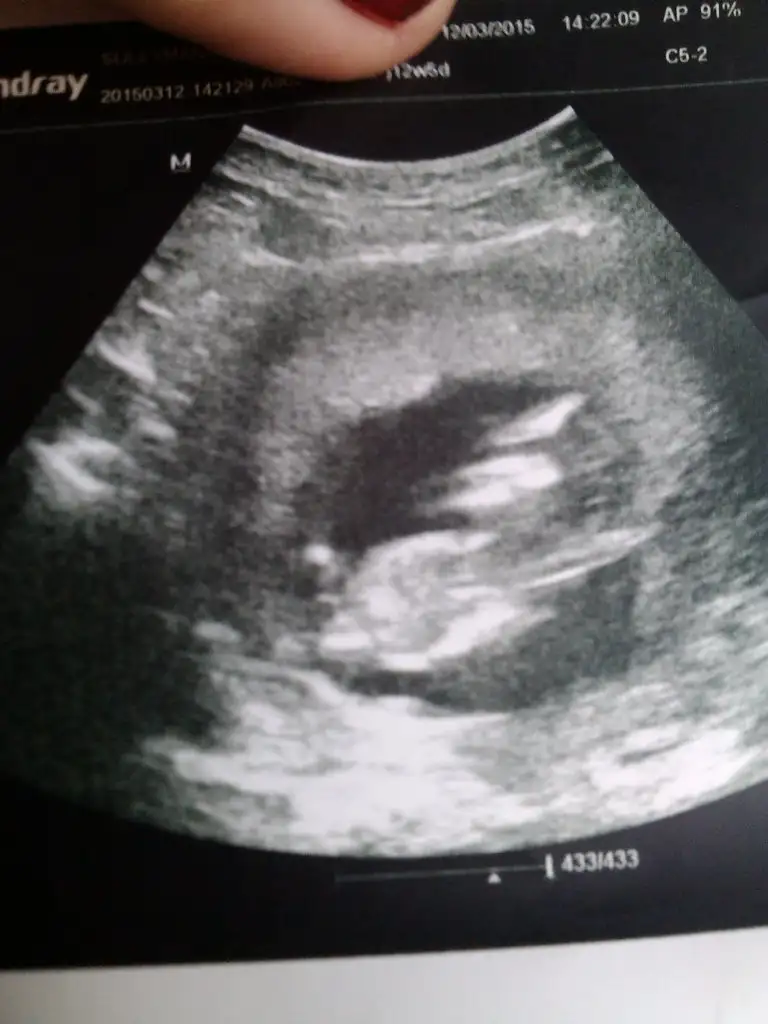

Kızlar ben de bugün ikili test için gittim. 4 gün önden gidiyoruz, 13+2'ymişizDoktor çok baktı bacak arasına bir şey söyledi ama kesin diyemeyiz dedi. Nub pek görünmüyor sanki, ben anlamadım. Bir de siz bakar mısınız, anlaşılıyor mu? Yoksa sonraki kontrol 4 hafta sonraaa Allah'a şükür sağlıklı görünüyormuş ama.. bu da yeter tabii..

Bakın biri 10+6 fotosu biri 13+2. Dönmüş de minikim